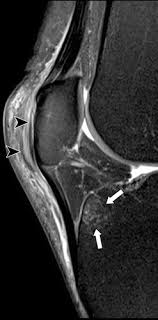

The muscles of the knee include the quadriceps, hamstrings, and the muscles of the calf. General anatomy and musculoskeletal system. The muscles of the knee joint are incredibly important. Anatomy, symptoms, and radiologic evaluation. Magnetic resonance imaging (mri scan): Anatomy of the knee is complex, through the use of magnetic resonance imaging, clinicians can diagnose ligament and meniscal injuries along with identifying cartilage defects, bone fractures and bruises. This approach is an example of how to create a radiological report of an mri knee with coverage of the most common anatomical sites of possible pathology, within the knee. View of the anatomical labels.

This mri knee cross sectional anatomy tool is absolutely free to use. View of the anatomical labels. Mri for evaluating knee pain in older patients: Magnetic resonance imaging (mri) is the modality of choice in diagnosing accessory muscles, delineating their relationship to conclusion. Click on the links to show each structure. Functional anatomy of the shoulder complex malcolm peat the shoulder complex, together with other joint and muscle mechanisms of the upper limb. This webpage presents the anatomical structures found on knee mri. Musculoskeletal radiology south texas radiology group.

This webpage presents the anatomical structures found on knee mri.